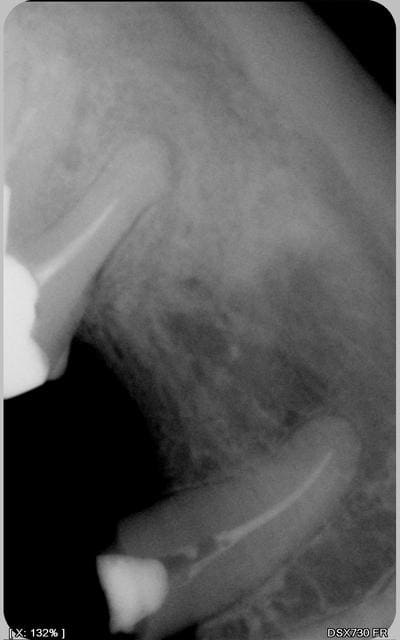

Pour la molaire, tu as un début de LPA, stade 2 voire 3 selon le PAI (péri apical index) sur la racine mésiale. Il me semble que ce soit plus cette dent qui soit en cause. Pas de bol, il semble que cette dent soit protégée par un IC. galére pour la dépose... :-(

Là où on ne peut te jeter la pierre c'est que ta dent est considérée en "bonne santé périapicale" si on fait référence à l'article concernant l'étanchéité coronaire dans le dernier ROS de la SOP. Les auteurs estimaient la bonne santé du périapex pour les indices 1 (aucune image), 2 ou 3; 4 et 5 étant considérés comme en mauvaise santé. Dans un post d'OCE, j'avais contesté cette définition, stéphane était de mon avis. La bonne santé périapicale, c'est l'indice 1 où il y a peanuts à l'apex, même pas un élargissement apical.

La racine mésiale de la molaire est à mon avis "malade". En tout cas, elle n'est pas en voie de guérison. Donc j'aurai fait la RTE, au pire, j'aurai perdu une heure de mon temps. Mais en cas de souci, au moins j'aurai la preuve que j'ai essayé de faire le maximum.

la radio complète de la molaire pourrait donner un éclairage supplémentaire axe du pivot distal?